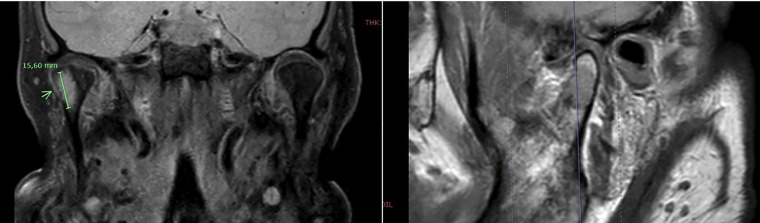

Case report: An 86-year-old woman with a history of oncocytic thyroid carcinoma treated with total thyroidectomy and radioactive iodine in 2019. During follow-up, elevated thyroglobulin levels were detected, and a PET-CT scan revealed uptake in the right mandibular condyle. The lesion was confirmed by magnetic resonance imaging and surgical biopsy and was treated with a right condylectomy. Histopathological analysis revealed bone infiltration by oncocytic carcinoma. The patient had a favorable postoperative course, with undetectable serum thyroglobulin levels after surgery.